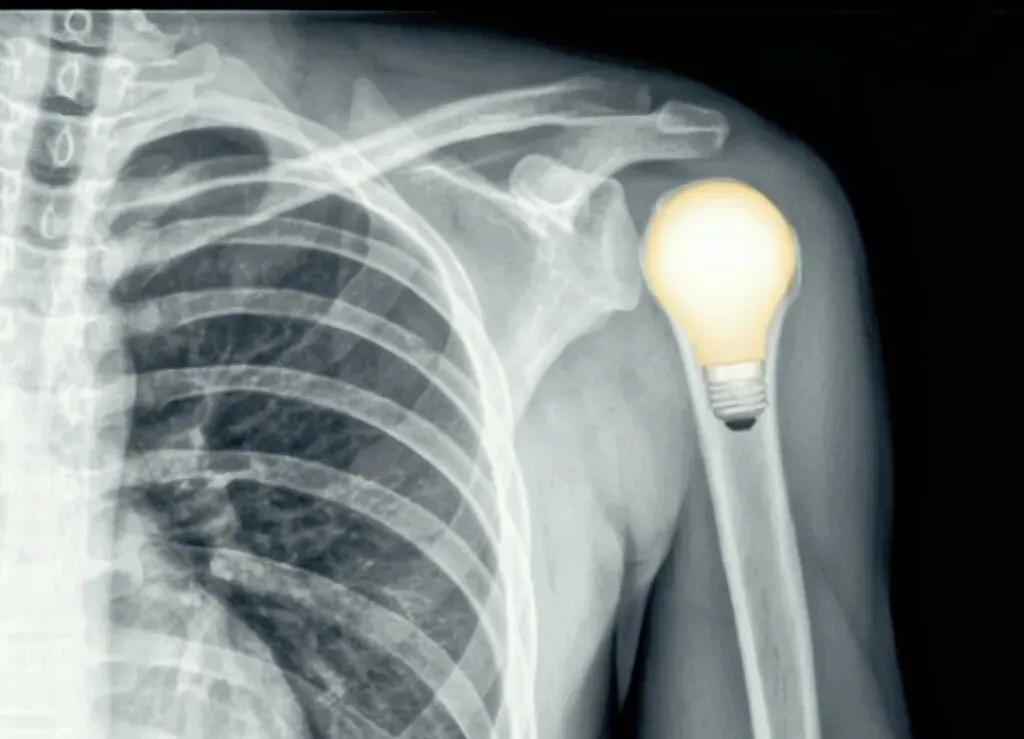

灯泡征是指在肩关节正位X线中存在后脱位可能的影像学表现。由于肱骨近端内旋,肱骨头的形态变圆,呈灯泡状,所以称为灯泡征。

常可伴肱骨内旋,肱骨头投影变圆呈灯泡征。肱骨内旋后,大小结节投影有时候会形成一条折线,称M字征。